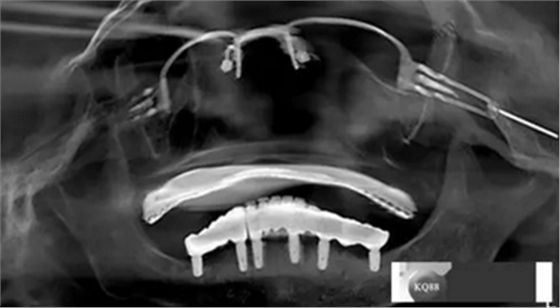

2)術前準備及手術過程,測量血壓及血糖,簽種植知情同意書;嚴格遵循無菌操作,局麻下采用微創(chuàng)技術于323436分別植入osstem4.0X10,4.0X10,4.5X7; 434446分別植入osstem4.0X1O,4.0X10,4.5X7.初期穩(wěn)定性均達到了35N.CM以上;嚴密縫合,止血,種植體位點和方向與設計一致。

戴牙:試戴,拍片確定邊緣密合后調整咬合,試戴一周后患者適應,咬合良好,基臺加力30N.CM,粘接劑粘固,去除多余粘結劑,拍片確定有無粘接劑殘留,并進一步微調咬合